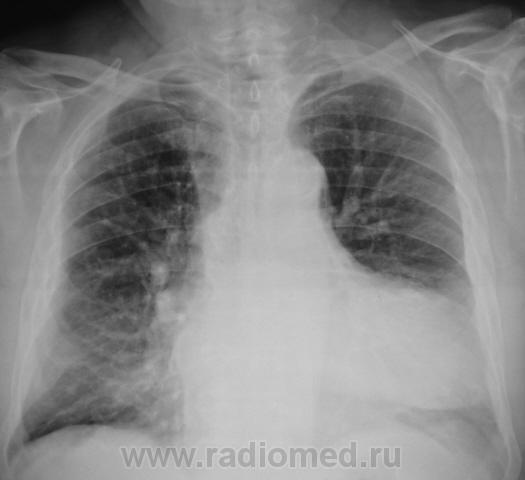

Пациент направлен на исследование ОГК с диагнозом "Экссудативный плеврит слева".

Версия, полагаю терапевтов, о плеврите интерсна. Вопрос другой - что же это за "зверь" в передне-медиальном отделе слева? И еще оболее интересное предположение, а связан ли "он" вообще с левым легким?...а не имеет ли "он" отношения к сердцу?

Честно говоря, никогда со столь необычной локализацией и формой осумкованого  плеврита не встречался...а в голове все время вертится неотвязная мысль "миксома????"...хотя это далеко не факт...

Валентин Львович, а ведь никто не сказал, что и слева не может быть целомических кист перикарда, в т.ч. и таких больших?

Вот и сложился пока небольшой диф.ряд. Думаю, коллеги тоже выскажутся по этому поводу.

Но в плане дообследования - однозначно необходимо КТ, хотя, УЗИ сердца тоже может внести кое какую ясность.

Ну к "соплям" такие изменения НИКАКОГО отношения не имеют; на пленке 100% образование было пропущено (приняли за гипертрофию левого желудочка, в лучшем случаеПодмигиваю).

Я думаю, многие вопросы может снять R-скопия лёгких. Странно, что при столь выраженных изменинеиях нет особой клиники...Скорее, изменения связаны с сердцем или перикардом, возможно какое-то доброкачественное образование(?).

Оказалось, что "надцать лет" тому (со слов зятя и врача, который надзирает за участком, где проживает пациент), пациенту был поставлен диагноз периферического рака лёгкого, тогда оперировать не решились, ожидали летального исхода. Но, пациент, несмотря на диагноз, чувствовал себя хорошо, вел довольно активный образ жизни, потолстел, и все дружно забыли за "диагноз", хотя, как уверяет участковый терапевт - "о диагнозе знает"

Сегодня созвонился с областной конторой, говорил с 1 замом, направляем пациента туда с предварительным диагнозом - "Миксома", рекомендовали КТ и всю прочую "онкологическую атрибутику".